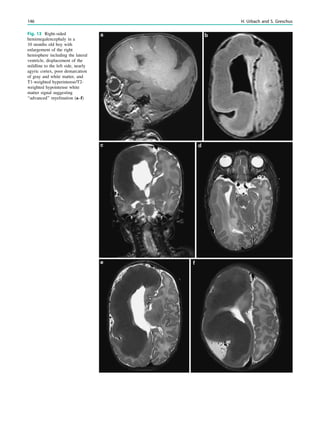

99–100

Ebeling U, Reulen HJ (1988) Neurosurgical topography of the optic

radiation in the temporal lobe. Acta Neurochir (Wien) 92:29–36

Egan RA, Shults WT, So N et al (2000) Visual field deficits in

conventional anterior temporal lobectomy versus amygdalohippo-

campectomy. Neurology 55:1818–1822